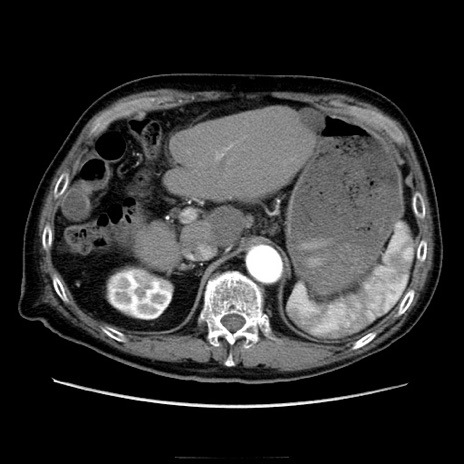

症例21(横断像)

【症例】70歳代男性

【主訴】腹痛

【現病歴】肝硬変・肝細胞癌にてかかりつけの方。約9時間前に食後より腹痛出現。症状が徐々に増悪し、嘔吐出現したため来院。

【既往歴】肝硬変、肝細胞癌(RFA、TACE後)

【身体所見】意識清明、表情苦悶様、BT 36℃、BP 129/78mmHg、P 88bpm、SpO2 97%(RA)、右上腹部から心窩部にかけて圧痛あり、反跳痛なし、筋性防御あり。

【データ】WBC 5800、CRP 0.16